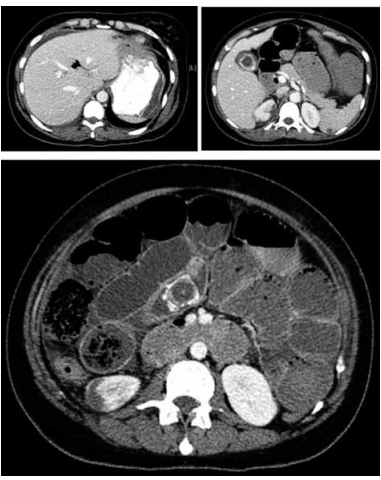

Mulher, 68 anos, comparece à unidade de emergência, queixando-se de dor e distensão abdominal nas últimas 24 horas, associados a múltiplos episódios de vômitos. Ao exame, apresenta-se sudorética, normotensa; abdome distendido, peristaltismo aumentado, difusamente doloroso. À palpação, sem sinais de irritação peritoneal. Refere ter constipação intestinal, sendo a última evacuação há cerca de 48 horas. História pregressa de múltiplos episódios, no último ano, de dor abdominal do tipo cólica, em hipocôndrio direito e epigástrio, menos intensa que a atual, com resolução espontânea, Foi realizada tomografia computadorizada do abdome.

Com base no quadro clínico da paciente e nos exames de imagem, qual o diagnóstico mais provável?